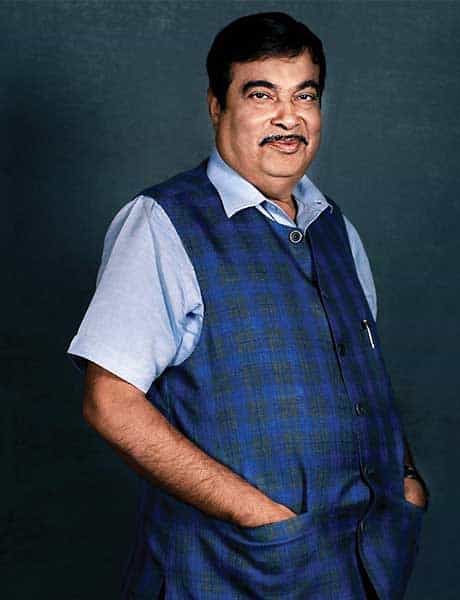

Nitin Gadkari

MUMBAI, INDIA

Surgery Type - Laparoscopic Gastric Bypass (LGB)

Surgery Date - September 12, 2011

Was a long standing, uncontrolled diabetic on high dose of insulin+ 3 oral anti diabetic medications, despite which his sugars were uncontrolled. In addition he was also hypertensive (high BP) & on regular medications.

Post-surgery – He is off insulin and medications for diabetes and blood pressure.